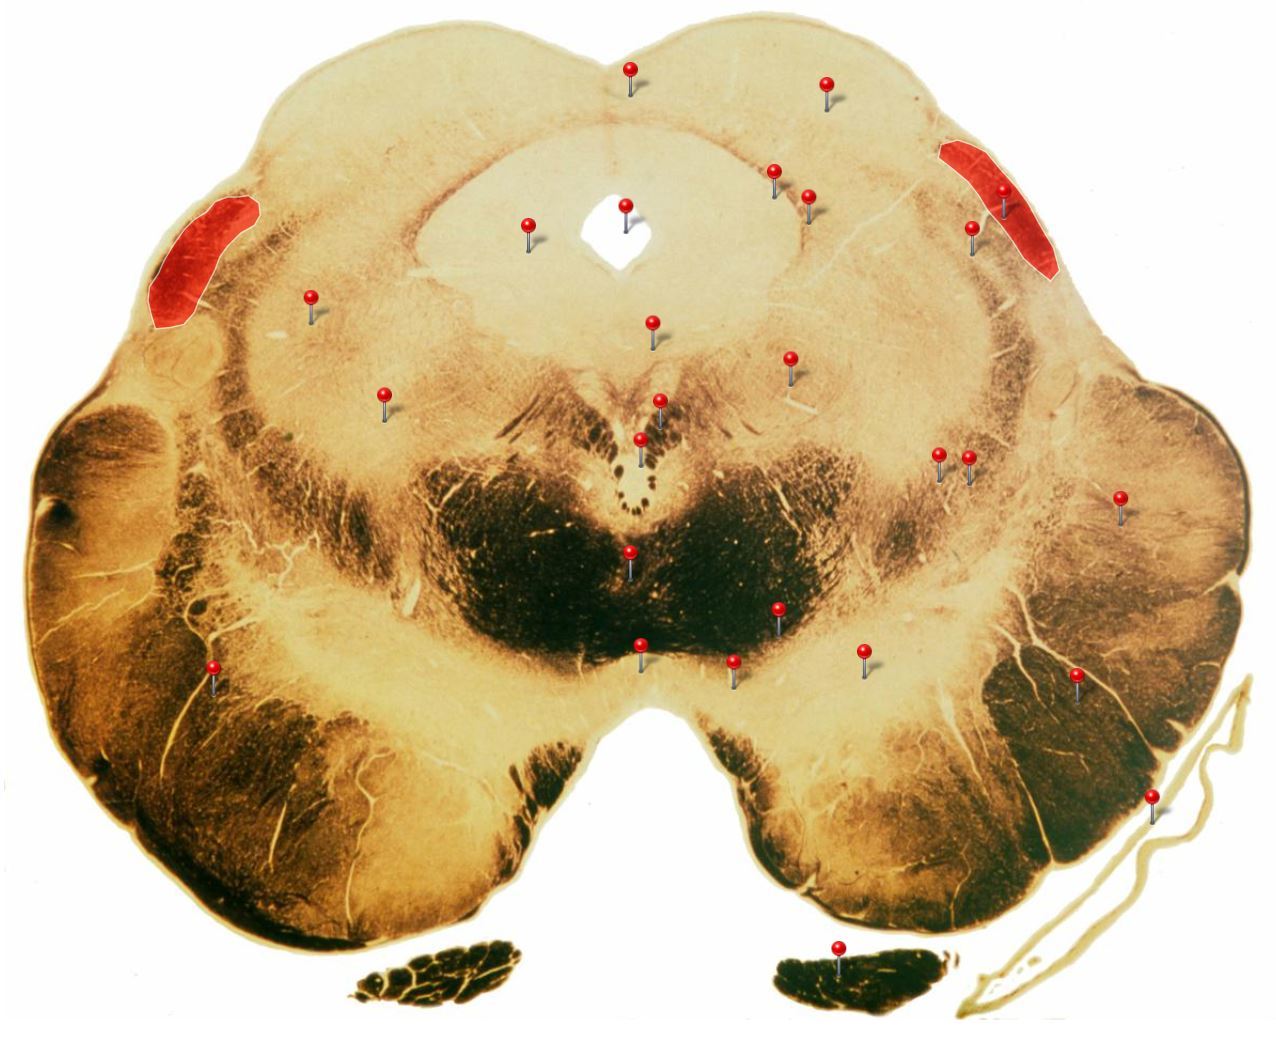

Corticospinal Tract

Rostral Medulla

Controls precision and speed of skilled movements involving the distal muscles of the contralateral limbs, particularly those of the hands and fingers

Nucleus Ambiguus

Neurons supply the muscles of the pharynx, larynx, upper oesophagus and heart

Basilar Artery

Provides blood supply to much of the cerebellum, pons, midbrain and posterior thalamus as well as part of the temporal (inferior surface) and occipital (medial and inferior surfaces) lobes

Olives

Elevations formed by the inferior olivary nuclei which integrate information from a variety of sources before relaying it to the cerebellum

Rubrospinal Tract

Assists in the control of movements of the hands and fingers

Medial Vestibular Nucleus

Process inputs from vestibular receptors of the inner ear and are involved in the regulation of posture and the coordination of head and eye movements

Spinal Trigeminal Tract

Transmits somatosensory (crude touch, pain and temperature) inputs from the Trigeminal nerve (CN V) through the midpons and medulla to the spinal trigeminal nucleus.

Ventral Cochlear Nuclei

One of the relay nuclei for the auditory fibres of the vestibulocochlear nerve (CN VIII) and functions to modify inputs to the higher auditory structures

Medial Longitudinal Fasciculus

Pathway through which eye movements are coordinated with changes in head position

Dorsal Cochlear Nuclei

One of the relay nuclei for auditory fibres of the vestibulocochlear nerve (CN VIII) and functions to modify inputs to the higher auditory structures

Inferior Olivary Nucleus

Plays an important role in the learning of new motor skills

Solitary Nucleus

Processes visceral afferent (GVA and SVA [taste]) inputs from CN VII, IX and X and relays them to the reticular formation and visceral efferent nuclei

Spinal Trigeminal Nuclei

Processes sensory inputs, particularly pain and temperature, from the head and neck and relays them to the ventral posteromedial nucleus of the thalamus

Inferior Vestibular Nucleus

Plays a role in the maintenance of balance and the coordination of eye and head movements

25

Medial Lemniscus Rostral Medulla Transmits sensations of **discriminative touch, vibration, proprioception** an **stereognosis** from the *gracile* and *cuneate nuclei* to the *ventral posterior nuclei of the thalamus*

26

Ventral Spinocerebellar Tract Rostral Medulla Provides feedback to the cerebellum concerning motor activity (including reflexes) in the lumbosacral levels of the spinal cord

27

Glossopharyngeal Nerve (CN IX) Rostral Medulla Transmits taste and tactile sensation from the posterior part of the tongue, pharynx and ear, and visceral sensation from the chemo- and baroreceptors of the carotid body and sinus (also supplies efferent fibres to the otic ganglion and stylopharyngeus m.)

28

Inferior Cerebellar Peduncle Rostral Medulla Formed by pathways passing in both directions between the medulla and cerebellum

29

Tectospinal Tract Rostral Medulla Function in humans not precisely determined; thought to mediate reflex movements of head in response to visual and perhaps auditory stimuli

30

Olivocerebellar Tract Rostral Medulla Transmits information from inferior olivary nucleus to the *contralateral* cerebellum, where it forms the **climbing fibres**

31

Lateral Vestibular Nucleus Rostral Medulla Contains cell bodies of the (lateral) vestibulospinal tract which regulates the activity of **axial** and **proximal** limb muscles in order to **maintain balance and posture**